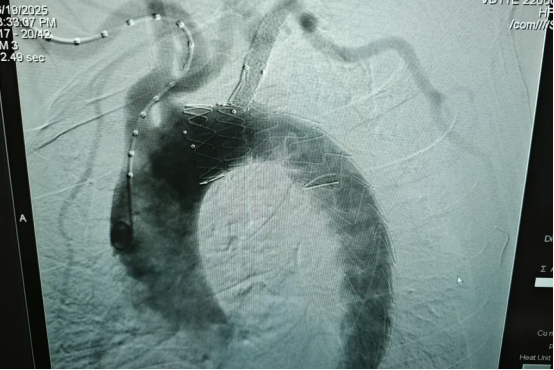

▲术后主动脉造影

手术历时2小时,手术团队通过造影定位主动脉壁间血肿的范围及髂动脉血栓情况,将“主动脉-左锁骨下动脉一体化支架”精准释放于病变位置,封堵血肿缺口,重建了安全的主动脉血流通道。术后造影显示血肿隔绝完全,重要分支血管血流通畅。该手术创伤少,对重要分支血管保留、减少内瘘有明显优势。